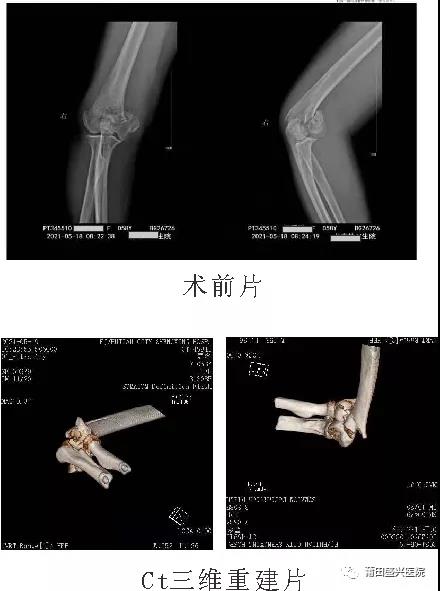

日前,有一女性患者王xx,右肱骨髁間粉碎性骨折,經(jīng)過與家屬及本人溝通后,我院業(yè)務副院長……